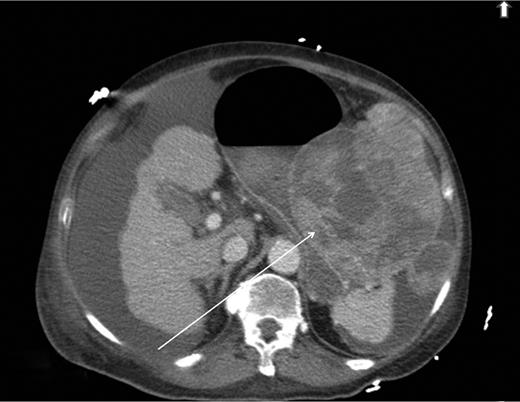

A computed tomography scan was performed which showed multifocal HCC with a large exophytic lesion invading into the greater curvature of the stomach (Figs. 3 and 4). Peritoneal metastases and ascites were present. The patient underwent an angioembolization of the hepatic tumour on the same evening. Angiography identified a replaced left hepatic artery as the dominant vessel supplying the lesion of concern in the left lateral hepatic segment (Fig. 5a). Gelfoam embolization was performed with no residual tumour enhancement thereafter (Fig. 5b).

Computed tomography image showing tumour originating from the liver.